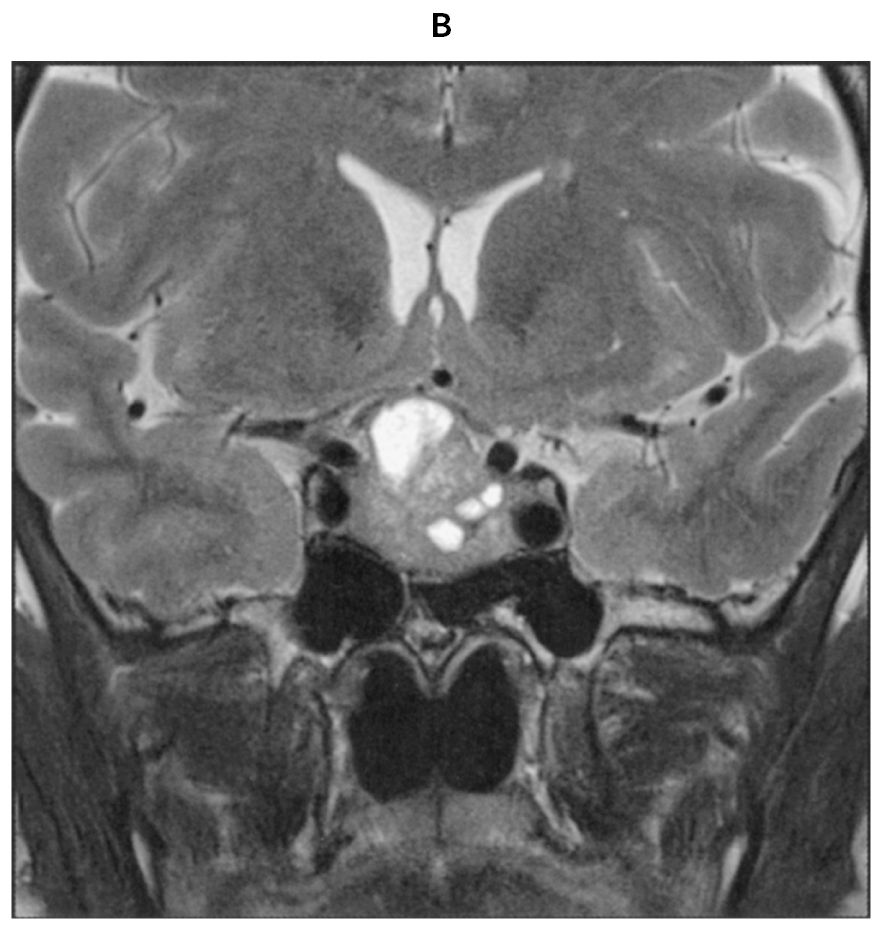

54歳の男性。口腔内の違和感を主訴に来院した。2年前から口唇の肥厚と下顎の突出を自覚し,その後,靴のサイズが約1cm大きくなり,指輪が外れなくなった。既往歴に高血圧症があり内服治療中である。また,睡眠時無呼吸症候群で通院中である。意識は清明。身長162cm,体重72kg。体温36.5℃。脈拍96/分,整。血圧120/90mmHg。矯正視力は右1.5左0.2。顔面は,眉弓突出,口唇肥大および下顎突出を認め,口腔内は舌の腫大を認める。血液所見:赤血球366万,白血球4,200,血小板20万。血液生化学所見:総蛋白7.6g/dL,アルブミン4.4g/dL,総ビリルビン0.6mg/dL,AST 18U/L,ALT 15U/L,尿素窒素22mg/dL,クレアチニン0.7mg/dL,空腹時血糖111mg/dL,HbA1c 6.3%(基準4.9~6.0),Na 140mEq/L,K 4.1mEq/L,Cl 104mEq/L。頭部造影MRIのT1強調矢状断像(A)と頭部単純MRIのT2強調冠状断像(B)とを下に示す。